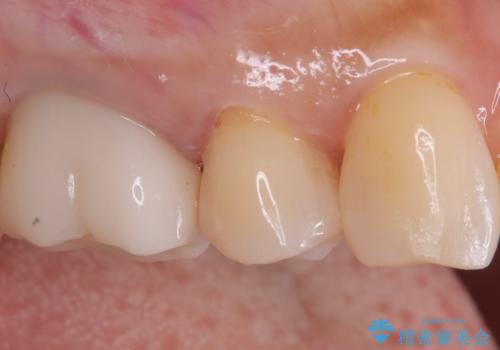

- 定期検診にてむし歯が見つかった患者さまです。

金属アレルギー体質とのことで、セラミックインレーにて修復治療を希望されました。

見た目も良く、満足していただきました。

セラミックインレーは、金属やプラスチックに比べ汚れが着きづらく、むし歯の再発リスクを減らすことができます。